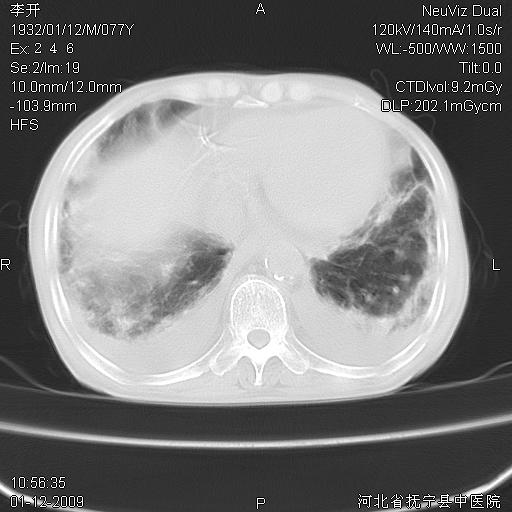

以下是引用黑白光影在2009-1-19 16:49:00的发言:[br]心衰肺水肿;心包、胸腔积液;冠脉钙化;肺部感染。